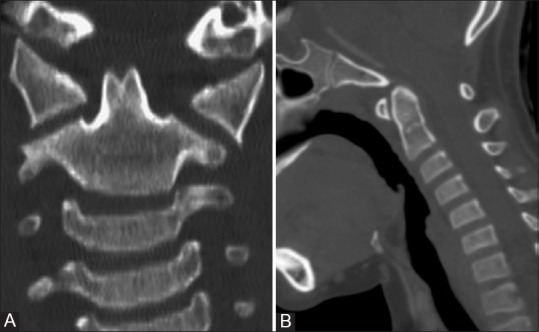

• Agenesis of the apical segment is the most common variety by comparison.

• Radiographically, the dens is short although there is usually adequate pivot height for the transverse atlantal ligament and there is thus no instability

• Instability found in

• floating apical ossicle

• Treatment of symptomatic cases is usually C1–C2 fusion.

A close-up of a scan of a human body AI-generated content may be incorrect.